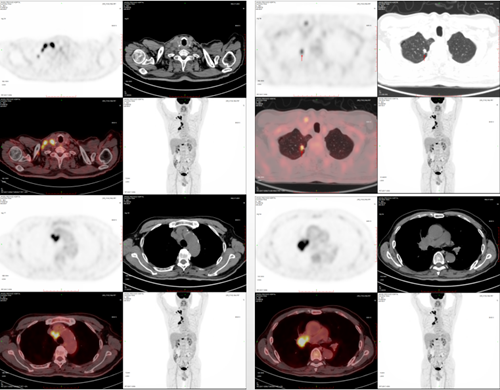

2024.9.27 PET-CT示:

◾ 1.右肺上叶尖段一不规则实性结节,牵拉胸膜,FG代谢增高;右侧下颈部、右侧锁骨区、右肺门(包括纵隔内第10R)及纵隔内第2R、3A组多发大小不等淋巴结,FDG代谢增高;左倒第9后肋及T12椎体溶骨性骨质破坏,FDG代谢增高;考虑右肺上叶周围型肺癌伴多发淋巴结、骨转移可能。

◾ 2.前列腺体积增大伴钙化,点状FDG代谢增高。

◾ 3.轻度脑萎缩。两肺及胸膜下多发肺气肿;两侧胸膜增厚。

◾ 4.多发椎体退行性变。

图1 2024.9.27 PET-CT结果